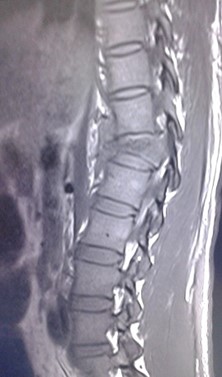

Volver a los detalles del artículo Espondilodiscitis tuberculosa. Presentación de un caso